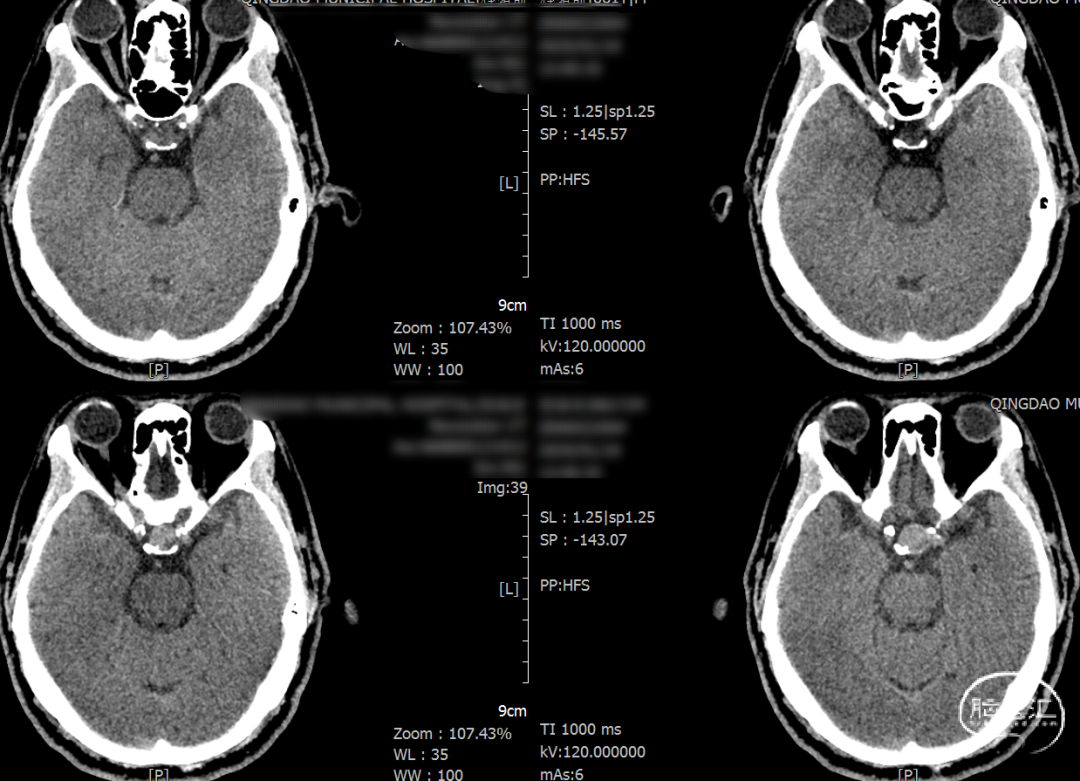

2025-1-19 DSA造影3D重建及方案讨论:

DSA造影3D重建测量

拟行脑动脉瘤密网支架置入术。

支架置入后造影显示,瘤内滞留明显,对侧造影几乎未见瘤内造影剂显影,手术结果满意。